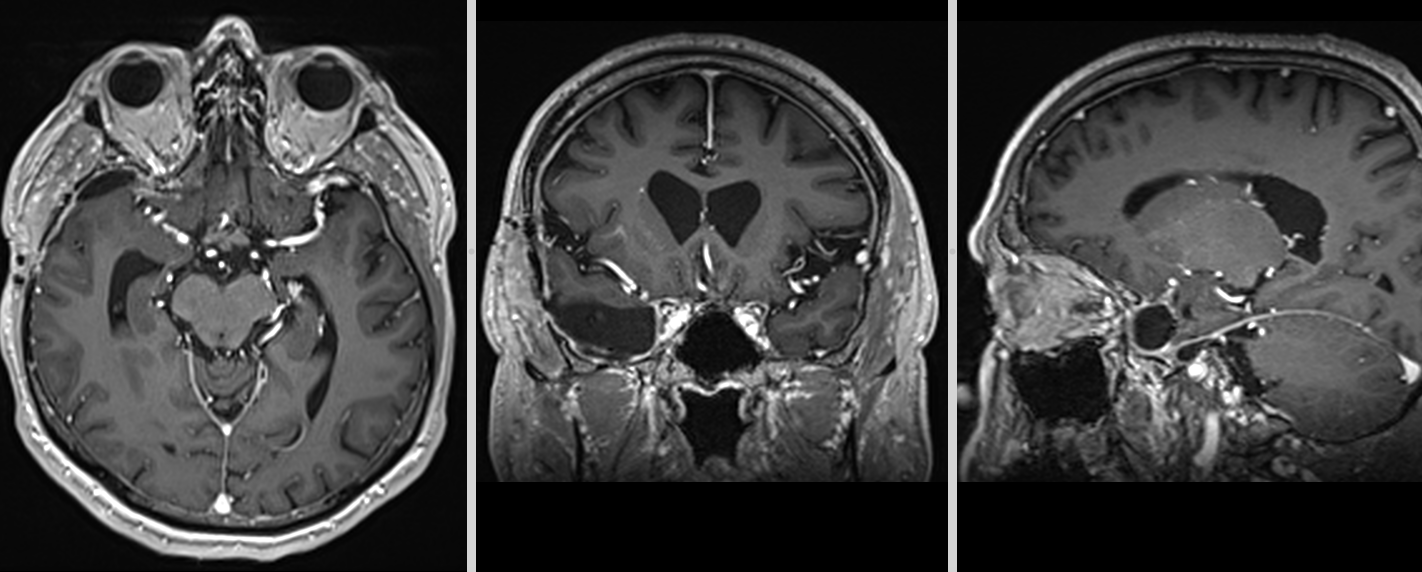

- RMN – cea mai completă investigație, oferă detalii despre relația cu țesutul cerebral, vasele de sânge și nervii Captarea substanței de contrast este deosebit de importantă.

- Angiografia – meningioamele sunt intens vascularizate si se vad bine la o angiografie; în plus, această tehnică permite și embolizarea tumorii – reducerea semnificativă a vascularizației tumorale prin injectarea unui gel special, ceea ce reduce sângerarea intraoperatorie și permite o intervenție chirurgicală în condiții mult mai bune.